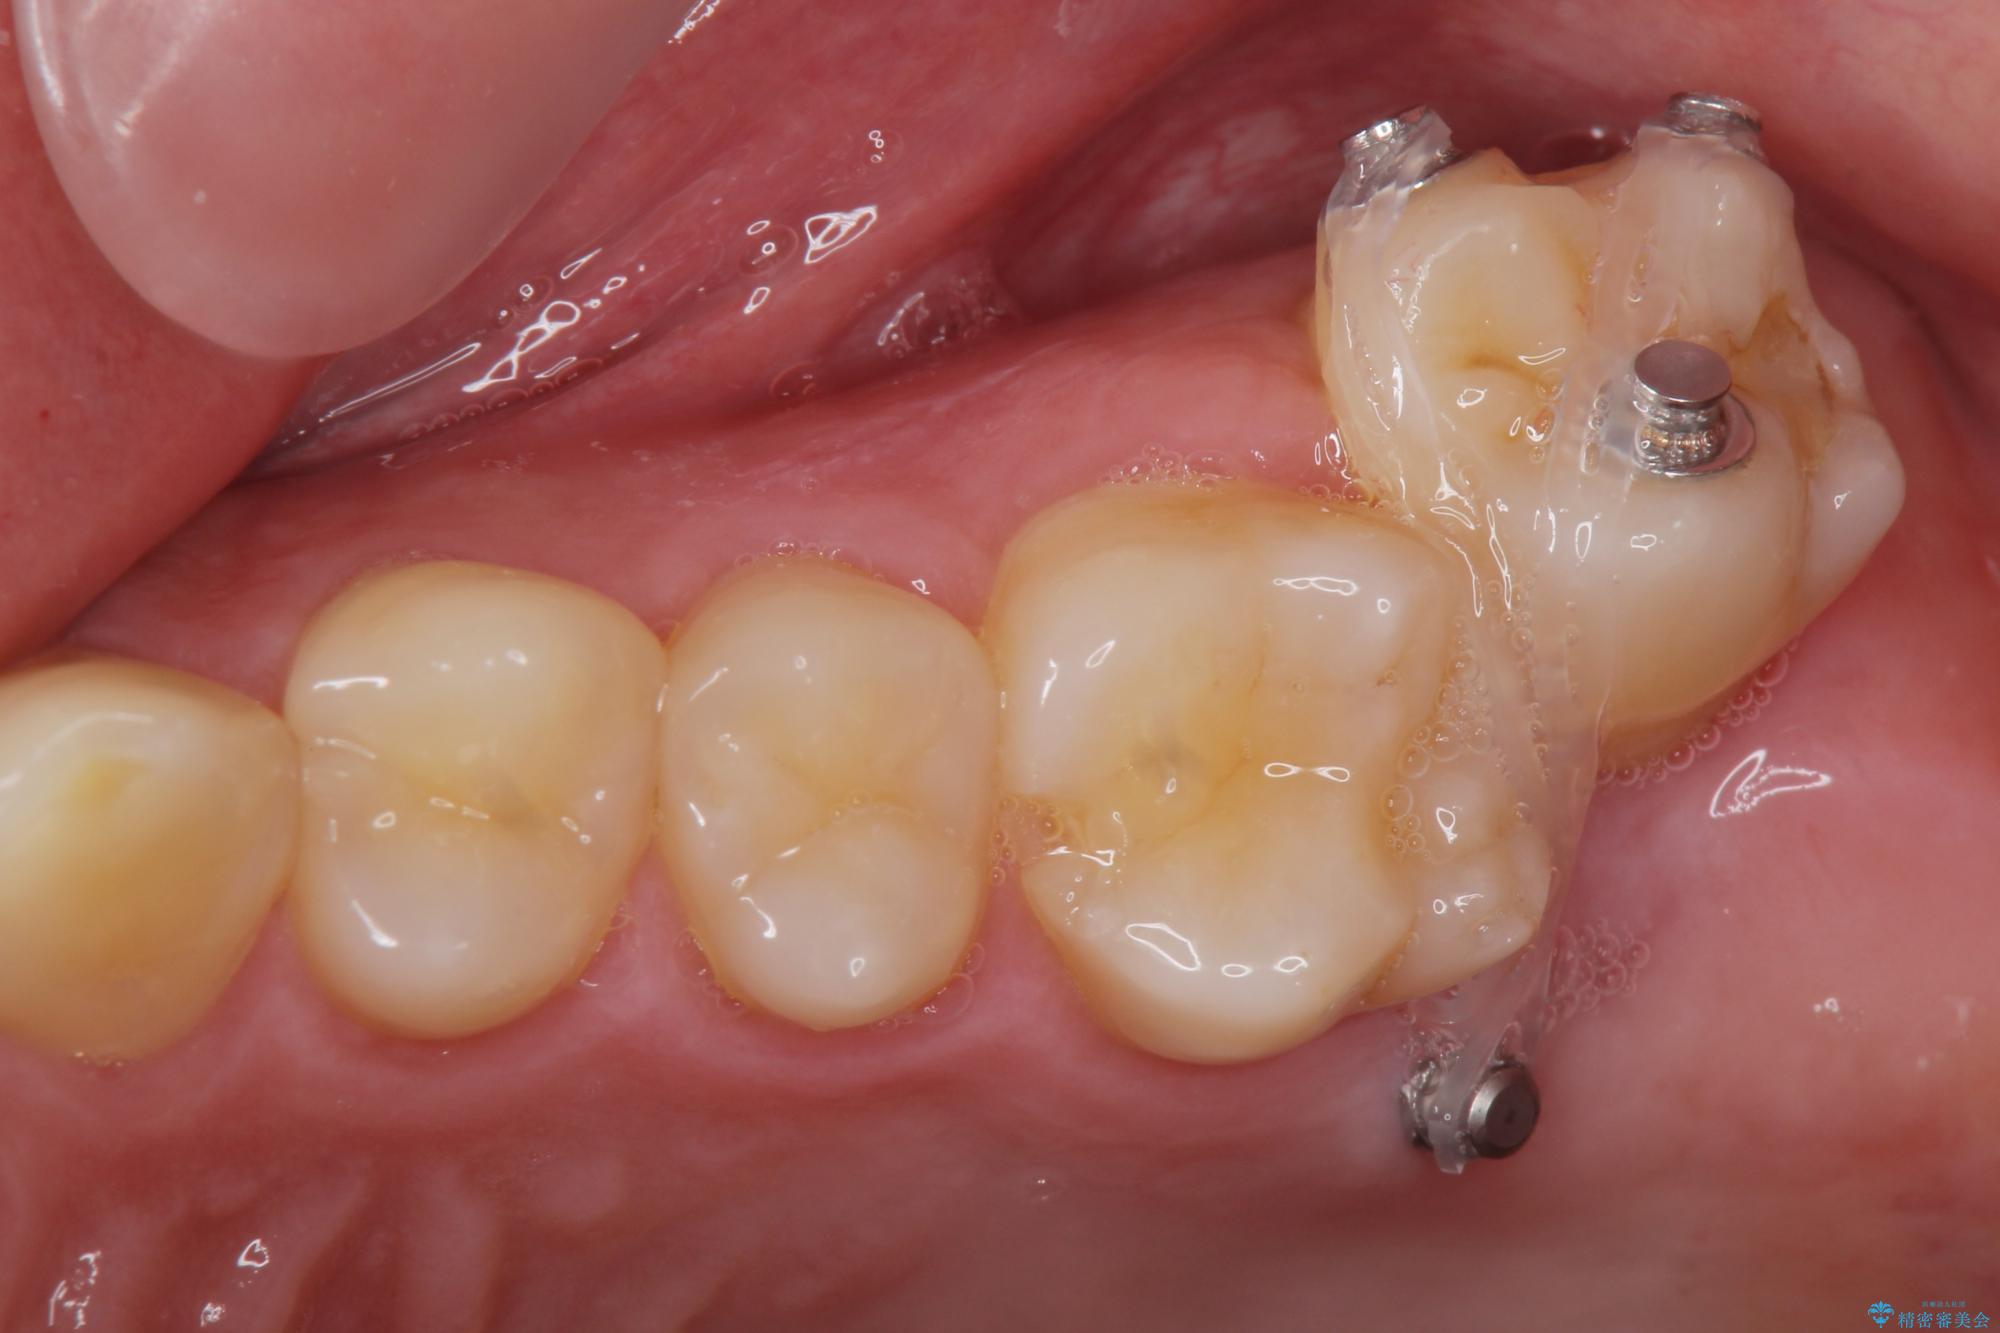

左上の奥歯がシザーバイトがありました。

部分矯正を行いシザーバイトを改善した後、インビザラインで歯列を整えました。